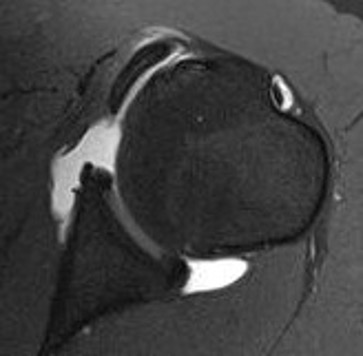

MRI